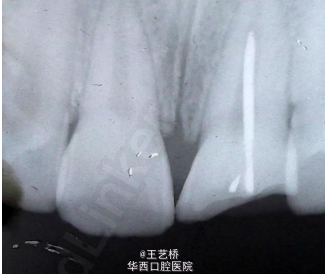

警惕孩子的不正常行为

小朋友对周围的一切事物难免会充满好奇,但是一旦出现不正常行为,大家就要警惕了。以下两个案例都是由于小朋友的不正常行为所造成的。